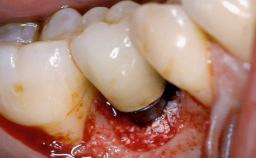

A 79-year-old female patient was referred to the Department of Periodontology of the University of Bern, Switzerland by her private dentist in May 2019. She had been rehabilitated in May 2005 with two tissue-level implants (Institut Straumann AG, Basel Switzerland) at sites 13 and 15, supporting a three-unit cemented fixed dental prosthesis (FDP). The metal-ceramic FDP had been cemented permanently with a glass-ionomer cement (Ketac Cem; 3M ESPE, Seefeld, Germany). Implant 13 had been diagnosed with peri-implant mucositis by the referring dentist in the course of regular supportive therapy. The patient was in good general health, did not smoke, and exhibited good self-performed plaque control.